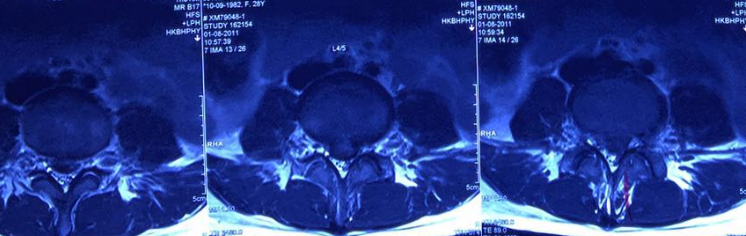

圖說 MR 1、 MR2

2011年8月嚴重腰部第四、第五節椎間盤突出。